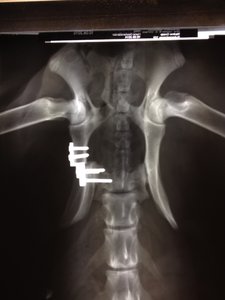

Abby humpelt und hinkt nach wie vor, keine wirkliche Verbesserung zu erkennen. Ich hab echt Schiss, dass sie durch ihre bescheuerten Aktionen die Schrauben gelockert hat (ich bin normalerweise nicht so schwarzmalerisch veranlagt) Ich muss sie 8 Stufen hoch und runter tragen, wenn wir Gassi gehen (40kg :shock